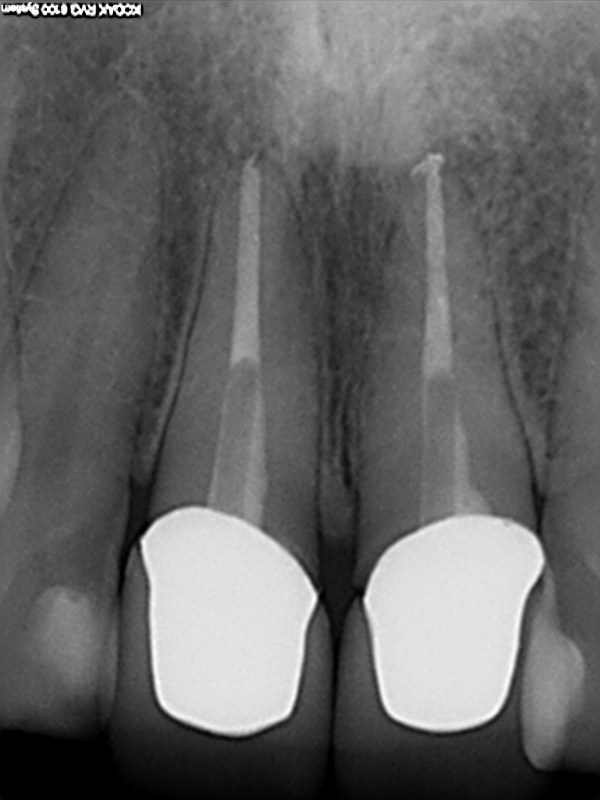

und wieder ein Recall

6 Monats Recall